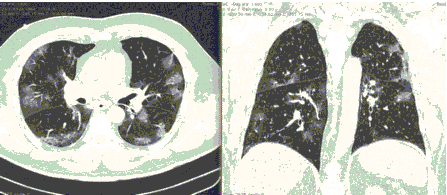

4.3. ЛУЧЕВАЯ ДИАГНОСТИКА COVID-19

Методы лучевой диагностики применяют для выявления COVID-19 пневмоний, их осложнений, дифференциальной диагностики с другими заболеваниями легких, а также для определения степени выраженности и динамики изменений, оценки эффективности проводимой терапии.

К методам лучевой диагностики патологии ОГК пациентов с предполагаемой/установленной COVID-19 пневмонией относят:

- Обзорную рентгенографию легких (РГ),

- Компьютерную томографию легких (КТ),

- Ультразвуковое исследование легких и плевральных полостей (УЗИ).

Стандартная РГ имеет низкую чувствительность в выявлении начальных изменений в первые дни заболевания и не может применяться для ранней диагностики. Информативность РГ повышается с увеличением длительности течения пневмонии. Рентгенография с использованием передвижных (палатных) аппаратов является основным методом лучевой диагностики патологии ОГК в ОРИТ. Применение передвижного (палатного) аппарата оправдано и для проведения обычных РГ исследований в рентгеновском кабинете. В стационарных условиях относительным преимуществом РГ в сравнении с КТ являются большая пропускная способность. Метод позволяет уверенно выявлять тяжелые формы пневмоний и отек легких различной природы, которые требуют госпитализации, в том числе направления в ОРИТ.

КТ имеет высокую чувствительность в выявлении изменений в легких, характерных для COVID-19. Применение КТ целесообразно для первичной оценки состояния ОГК у пациентов с тяжелыми прогрессирующими формами заболевания, а также для дифференциальной диагностики выявленных изменений и оценки динамики процесса. КТ позволяет выявить характерные изменения в легких у пациентов с COVID-19 еще до появления положительных лабораторных тестов на инфекцию с помощью МАНК. В то же время, КТ выявляет изменения легких у значительного числа пациентов с бессимптомной и легкой формами заболевания, которым не требуется госпитализация. Результаты КТ в этих случаях не влияют на тактику лечения и прогноз заболевания при наличии лабораторного подтверждения COVID-19. Поэтому массовое применение КТ для скрининга асимптомных и легких форм болезни не рекомендуется. При первичном обращении пациента с подозрением на COVID-19 рекомендуется назначать КТ только при наличии клинических и инструментальных признаков дыхательной недостаточности (SpO2 < 95%, ЧДД > 22).